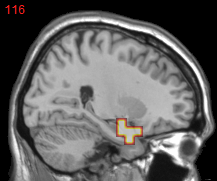

Figure 2: Feature selection by different models. The top row illustrates selected voxels in a 3D model (voxels with positive β𝛽\beta are in brown and negative ones are in blue), the mid and bottom rows illustrate the corresponding projections on brain slices.

Feature selection. For each task, the selected features are those whose β𝛽\beta are not zero . In Figure 2, the result of 30ADNC is used to illustrate the feature selection by different models (using the parameters at their best accuracy). As shown, the selected voxels by both GFL and n2superscript𝑛2n^{2}GFL cluster into several spatially connected regions, whereas those of lasso and T-test/MLDA scatter around. Also, as mentioned before, the LapL tends to select much more voxels than necessary due to the l2subscript𝑙2l_{2} regularization. Moreover, the selected voxels by GFL and n2superscript𝑛2n^{2}GFL are concentrated in Hippocampus, ParaHippocampal gyrus (which are believed to be the early damaged regions). On the other hand, the lasso and T-test/MLDA either select less lesion voxels or select probably noisy voxels not in the early damaged regions.